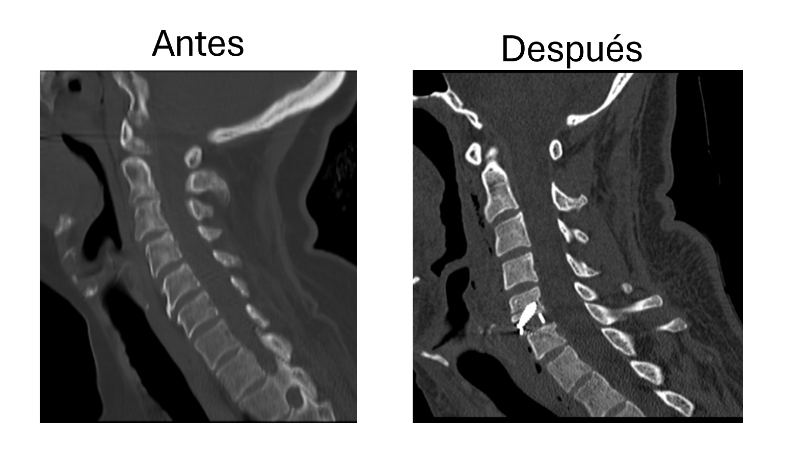

Abordaje cervical anterior con colocación de caja intersomatica C5-C6

Después de años con dolor intenso y limitación en el cuello, me realizaron un abordaje cervical anterior con colocación de caja intersomática en C5-C6. La recuperación fue rápida y el alivio fue casi inmediato. Volví a mis actividades sin molestias. Estoy muy agradecido con el equipo médico.